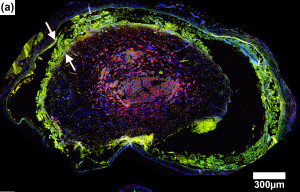

Using histological and immunocytochemical analyses, good biocompatibility of the magnesium implants was observed, with good development of regenerating nerve mini-fascicles and only mild inflammation in tissues even after complete degradation of the magnesium.

Figures A-D: Immunostained regenerating tissues after 6 weeks; (a and b) mid-conduit sections were stained for GLUT1 (green)/S100 (red)/DAPI (blue) in (a) NoMgSa and (b) MgSa animals (*cavity left by Mg, arrows delineate conduit material, bar=300μm). (c and d) Regenerating nerve mini-fascicles, indicated by arrows, run close to the Mg cavities, which are marked by * and arrowheads. The same staining was done on the section in (c), while the section in (d) was stained with ED1 (green)/NF200 (red)/DAPI (blue). Note GLUT1þ perineurium in (c) and thin layer of ED1+ macrophages above arrowheads in (d) (bar in c and d=50μm).

NoMgSa: saline filler only; MgSa: saline and Mg; GLUT1: glucose transporter 1; DAPI: 4’ 6-diamidino-2-phenylindole.2

Reproduced by permission of SAGE Publications Ltd., London, Los Angeles, New Delhi, Singapore and Washington DC.